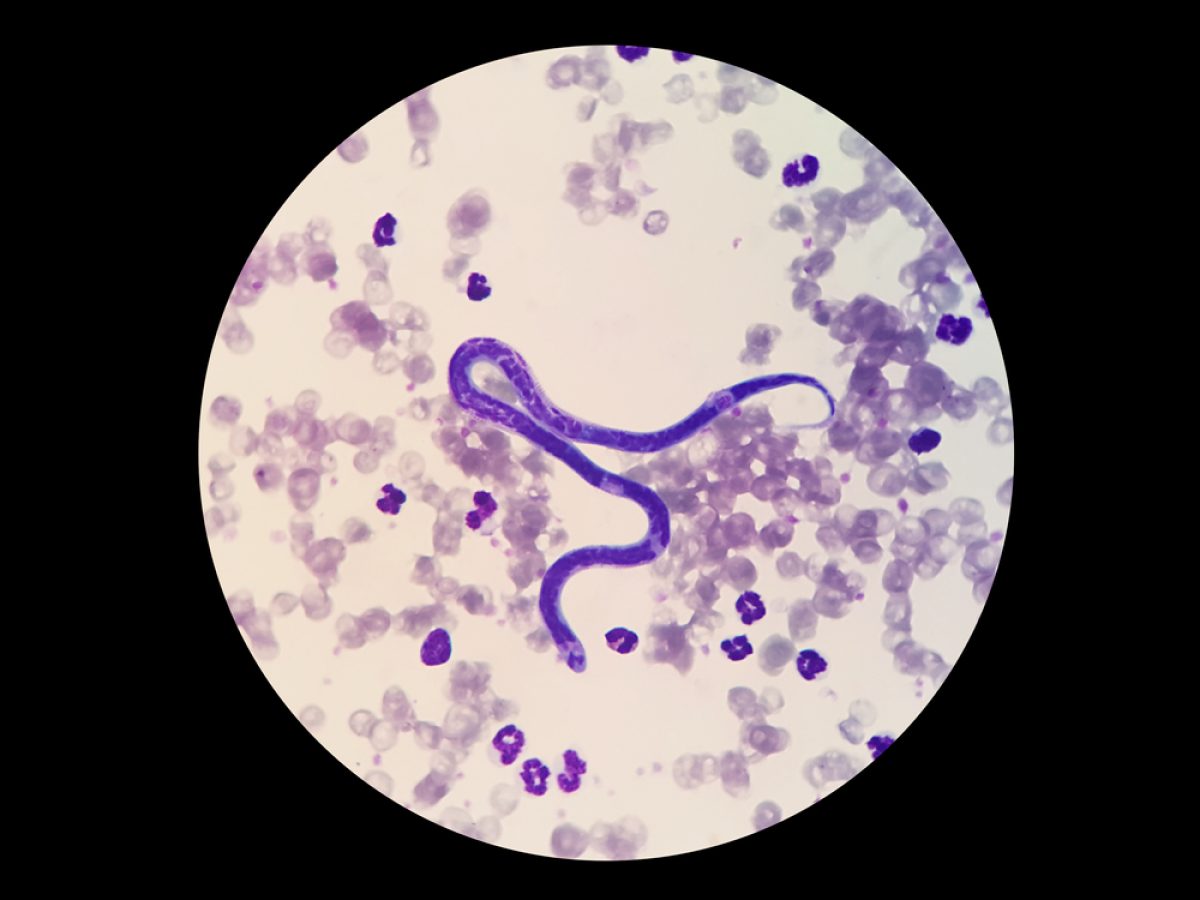

Ao contrário do que muita gente pensa, os vermes se alojam em diversos órgãos, e não apenas no sistema digestivo.

Dirofilaria immitis se instala no coração.